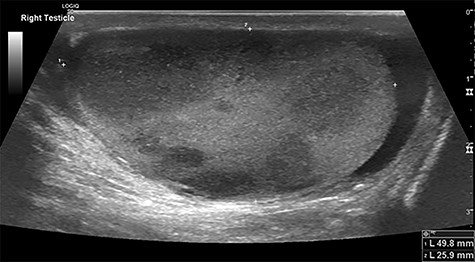

Intraoperatively, he developed new t-wave inversion on lead II of the 3-lead electrocardiogram (ECG). This resolved post-operatively, and he denied chest pain. He was kept in overnight for observation. The next morning, during the round, he reported central crushing chest pain the previous day that he had not disclosed. His ECG was repeated and demonstrated the t-wave inversion in lead II—indicating dynamic ECG changes. A troponin I level measured 27. As such, management for a non-ST elevation myocardial infarction was initiated and a cardiology consult organized, who advised continued acute coronary syndrome (ACS) treatment and an echocardiogram. This demonstrated a ‘pericardial mass (subcostal 3 cm × 2.5 cm) encroaching and extending outwards on both sides of the right atrioventricular groove’. ACS protocol was stopped and a cardiac magnetic resonance imaging (MRI) was organized (Figs 2 and 3).

Cardiac MRI (transverse plane) demonstrating an enhancing lesion surrounding the chambers of the heart.

This demonstrated a bulky mediastinal tissue (measuring 50% of the heart) that encased all the aorta and pulmonary artery as well as the coronary artery. It has malignant behaviour with multiple foci that breached fascial planes. It restricted the long axis of the heart but was not causing haemodynamic occlusion. It was non-resectable.